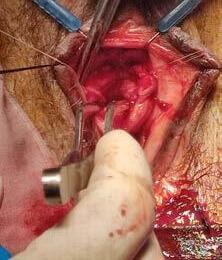

MANEJO DE LA ESTENOSIS URETRAL FEMENINA CASO CLINICO

Dr. Wellington A. Ledesma Cáceres

Dra. Yiraldy Merán Encarnación

P. 90